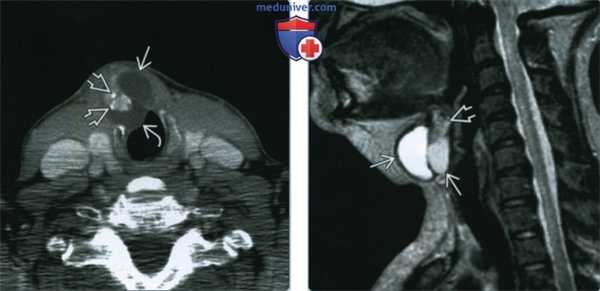

(Слева) КТ с КУ, аксиальная проекция. Рак щитоязычного протока. Кистозное образование располагается парамедиально в подсвязочном отделе, прорастая в подподъязычные мышцы. Кистозный компонент расположен под слизистой оболочкой подсвязочного отдела гортани. Во внешнем отделе этой кистозной опухоли определяется накапливающий контраст узел, в толще которого имеются кальцификаты.

(Справа) МРТ Т2ВИ в сагиттальной проекции. Кистозное образование, расположенное ниже подъязычной кости. Расположенный выше солидный узел имеет сигнал от промежуточного до низкого. Этот узел, накапливающий контраст, оказался карциномой щитоязычного протока.